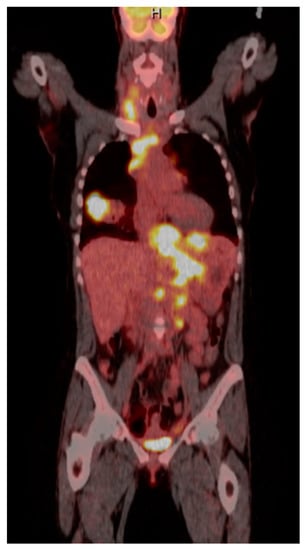

| 1 | F | 66 | Skin | Fundus, cardia, and body | Polypoid lesions with superficial ulcers | Esophagus, duodenum, mediastinum, cervical soft tissue, pancreas | Metastatic malignant melanoma | Radiotherapy and immunotherapy | Comfort care and death 5 days after EGD diagnosis of metastasis |

| 3 | F | 35 | Lung | Fundus | Fungating mass | Esophagus, mediastinum | Large-cell neuroendocrine carcinoma | Chemotherapy-carboplatin/ etoposide | Death 1 month after EGD diagnosis of metastasis |

| 4 | F | 73 | Kidney | Fundus and body | Multiple large friable masses | Liver and lungs | Clear cell renal carcinoma | Nephrectomy, chemotherapy, immunotherapy (Axitinib) | Death 10 days after EGD diagnosis of metastasis |

| 5 | M | 76 | Lung | Body | Cratered ulcers | Liver, bone and adrenals | Small cell carcinoma (poorly differentiated neuroendocrine Ca) | None | Death 7 days after EGD diagnosis of metastasis |